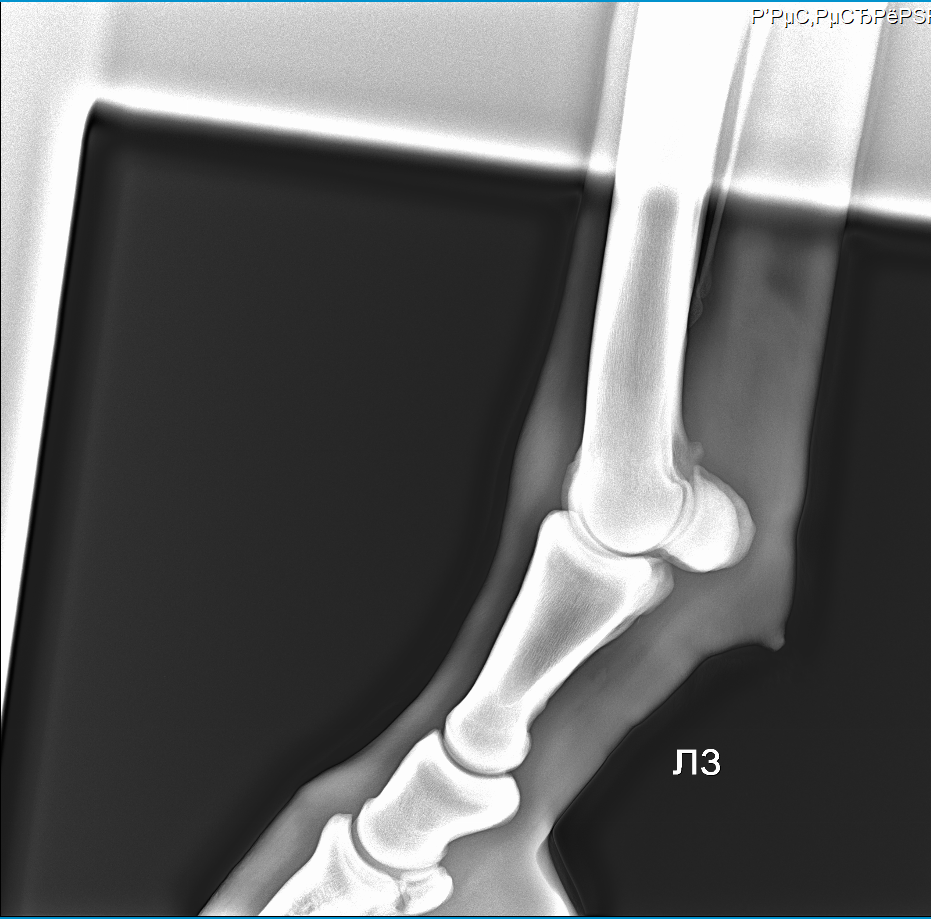

Пока шагали заметили одну интересную особенность, буквально не задолго до приезда Аркадия. Увидели что увеличился венечный сустав на задних ногах.В качестве наглядного примера сравнили ноги 2018/2019.Фото приложу.

Если быть краткой и по делу, то по приезду Аркадия провели тест, тест показал венечный ,а не скакательный сустав. По рентгену нашли артроз. Показали фото ног в сравнении, но кажется если бы не показали он бы не обратил внимания. Причина - то самое отмахивание ногами во время кормешки и попадание в стенку.